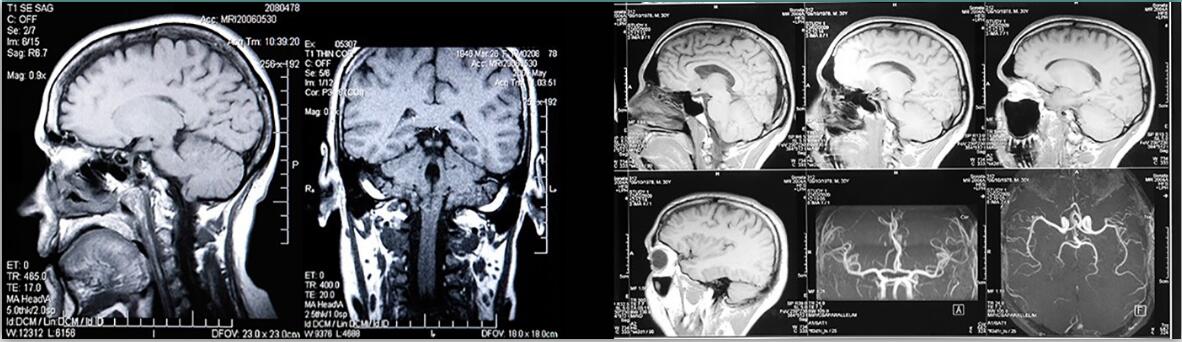

顱內(nèi)血管流動(dòng)模型,亞克力

顱內(nèi)血管流動(dòng)模型

該流動(dòng)模型旨在真實(shí)準(zhǔn)確地模擬顱內(nèi)脈管系統(tǒng)的真實(shí)血管直徑、血管長(zhǎng)度和復(fù)雜幾何形狀,在基底分叉處具有可選的經(jīng)典漿果球動(dòng)脈瘤,直徑可達(dá) 12.5 毫米。

與我們的 CompuFlow 1000 或 CompuFlow 1000 MR 一起使用時(shí)測(cè)試成像技術(shù)幾何保真度的里想模型